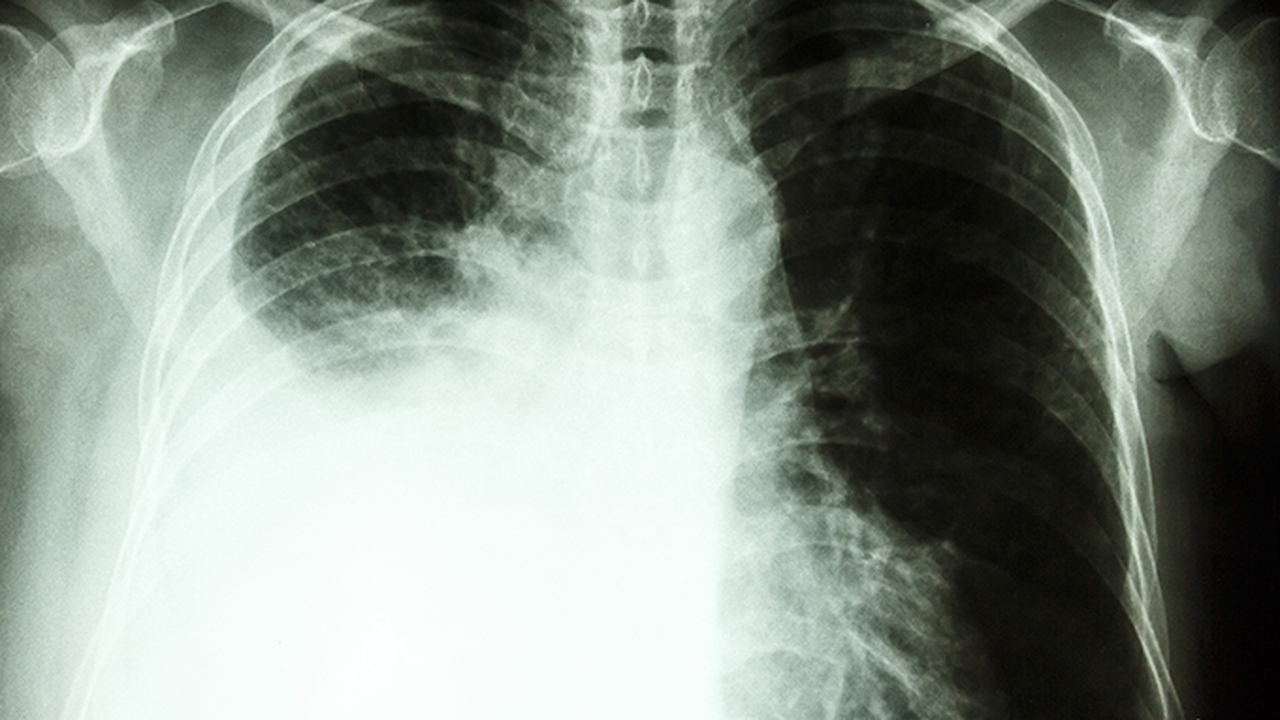

矽肺病是由于长期吸入二氧化硅粉尘引起的职业性肺部疾病,主要表现为咳嗽、胸闷、呼吸困难等症状。早期诊断和规范治疗对延缓病情进展至关重要。